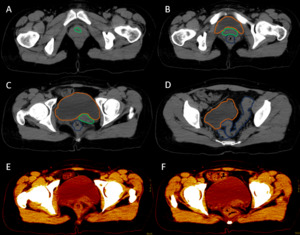

After analyzing the tomographic reports, the findings described in each of them were found in the cervical vertebrae (IMAGE 1), vertebral column (IMAGE 2), and abdomen (IMAGES 3 and 4). Karyotype report described in IMAGE 5.

With the above, diagnoses of: MURCS association (uterine, tubal, cervical and upper two-thirds of the vagina aplasia, renal aplasia and spinal dysraphism in cervical and lumbar vertebrae, as well as scoliosis), hypothyroidism and hyperprolactinemia were integrated. The patient was questioned about her reproductive desire; however, she did not want it. She was sent to an outpatient spine clinic for evaluation, and to nephrology for close and educational follow-up. She was scheduled for an appointment in three months with a new hormonal profile, for possible modification of the established treatment, and to consider starting a dopamine agonist.

**_there_is_right_renal_agenesis__t.png)